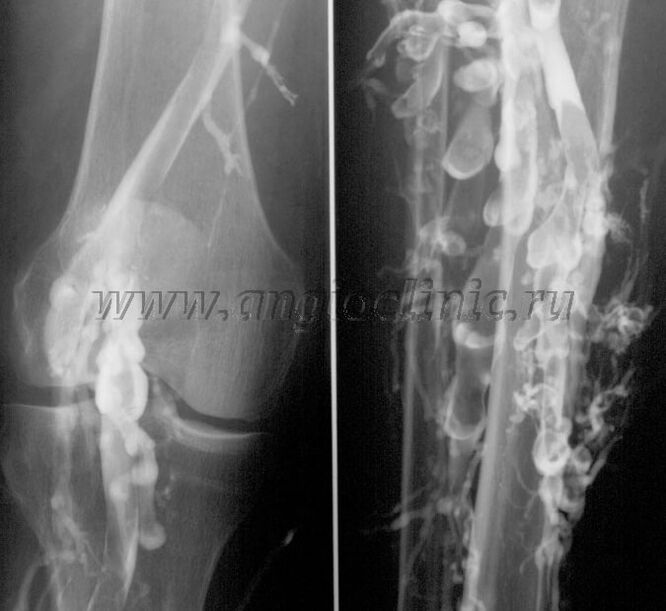

Contrast venografie

Meestal is echografie voldoende voor een volledige diagnose van veneuze pathologie, maar in sommige gevallen is het noodzakelijk om de relatie tussen de toestand van het diepe en oppervlakkige veneuze systeem te bestuderen, vooral in het geval van recidieven van spataderen en secundaire spataderen.

Echografie scannen

Om deze problemen op te lossen, wordt contraströntgenonderzoek gebruikt. De saphena worden doorboord en er wordt contrast toegediend. De beweging van het contrast wordt waargenomen op de monitor van het röntgenapparaat en alle noodzakelijke tests en projecties worden uitgevoerd. Momenteel wordt venografie voor spataderen zeer zelden gebruikt.